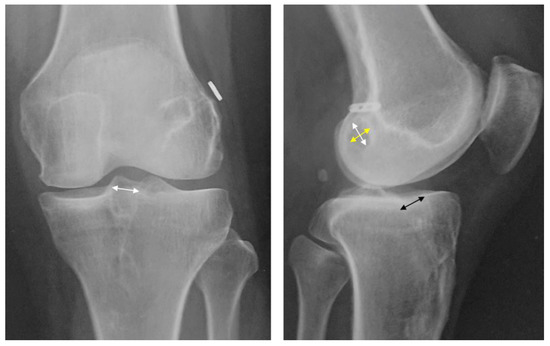

2.2. Radiograph Evaluations